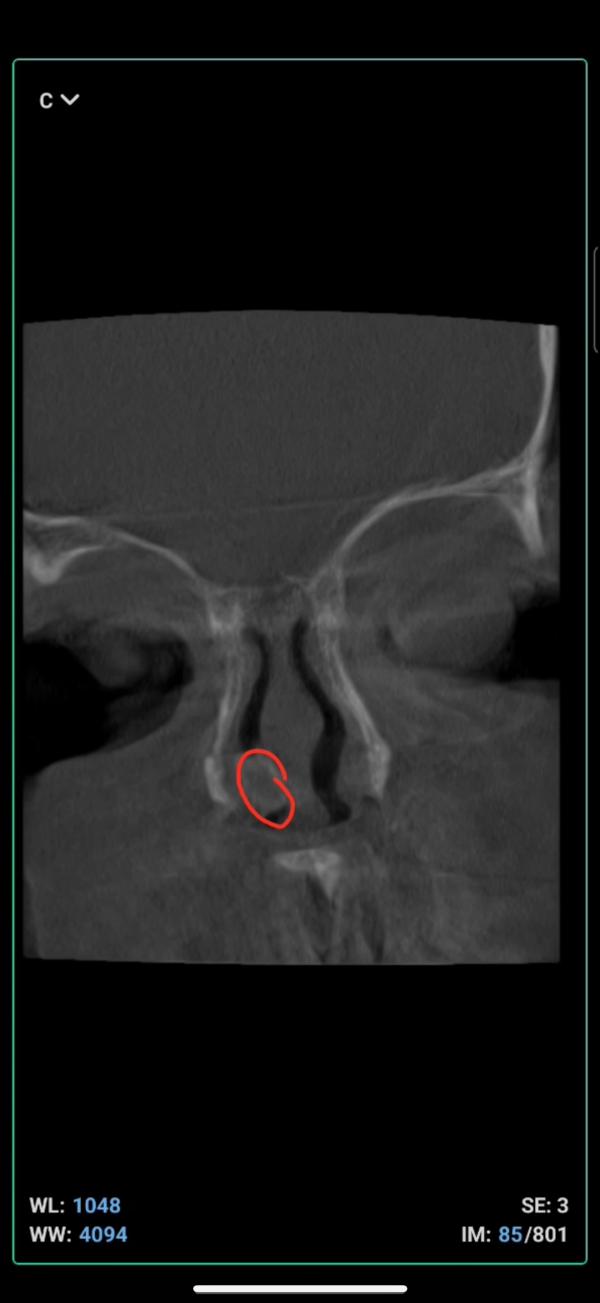

может кто сталкивался с таким? у теймии обнаружили образование в носу. думали что-то такое, что можно прочистить, но нет. лор отправил на 3Д снимок, и сказал что нужно удалять. но что это такое он не может сказать

Может врождённая неразделённая перегородка

Если это полип, он был у моей дочери, были на приеме у Адама Залимхановича, прописал лечение, курс аб, полип рассосался👐🏻